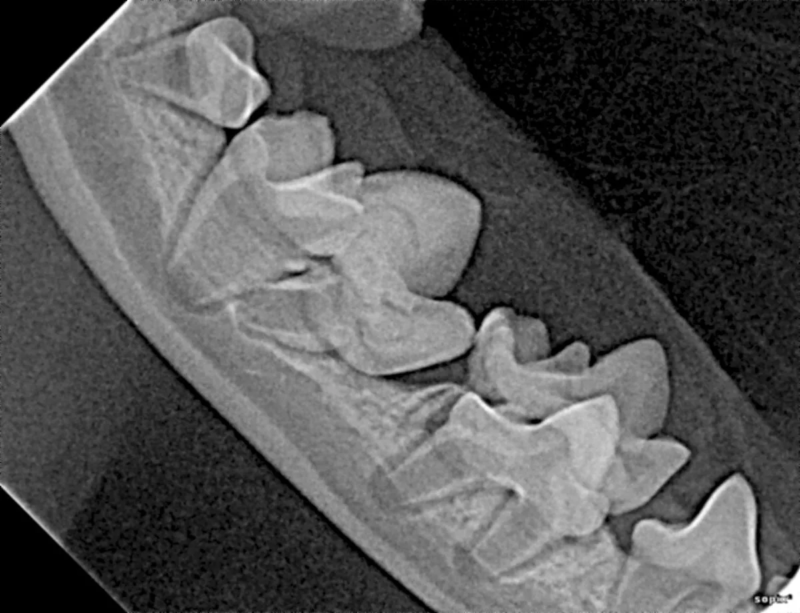

Cone Beam Computed Tomography

The Center now provides advanced imaging via cone beam CT. Cone beam CT is excellent for visualization of bony structures of the skull, nasal cavity, teeth, and ears. Cone beam CT is especially helpful for diagnosing dental disease and evaluation of jaw fractures. It can also be useful for evaluating the sinuses and tympanic bulla. Cone beam CT can be used in conjunction with nasal biopsy and culture to evaluate nasal discharge whether chronic or acute.